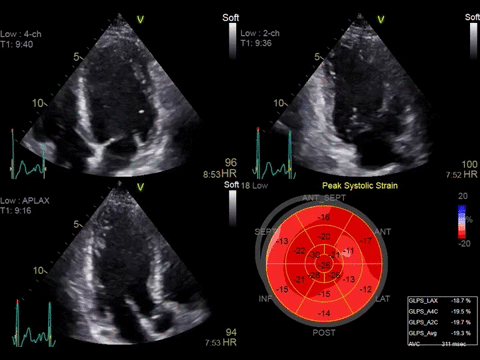

• Автоматическая оценка регионарной сократимости миокарда левого желудочка с расчетом большой группы параметров с помощью функции Automated Function Imaging (AFI).

• Протоколы AFI Stress, позволяющие получать стандартные апикальные проекции в двумерном режиме и рассчитывать регионарную и глобальную продольную деформацию миокарда на всех уровнях нагрузки.

• Функция 4D Strain для расчета глобальной и регионарной деформации миокарда на основе алгоритма пространственного спекл-трекинга, отображаемая в виде диаграммы «бычий глаз».

• AFI - режим цифровой недопплеровской качественной и количественной оценки региональной сократительной функции ЛЖ.

• Myocardial Work - модуль дополнительной качественной и количественной оценки глобальной и региональной сократительной функции миокарда левого желудочка, взаимосвязи систолической продольной деформации и давления.